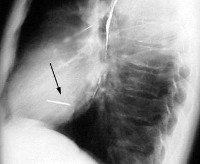

Рентгенография сердца позволяет идентифицировать рентгеноконтрастное инородное тело, уточнить его местоположение и размеры, установить количество, если имеется несколько объектов. По данным рентгенографии определяются размеры сердца, крупные сосуды, их положение, их форма, наличие патологических образований и их смещение.